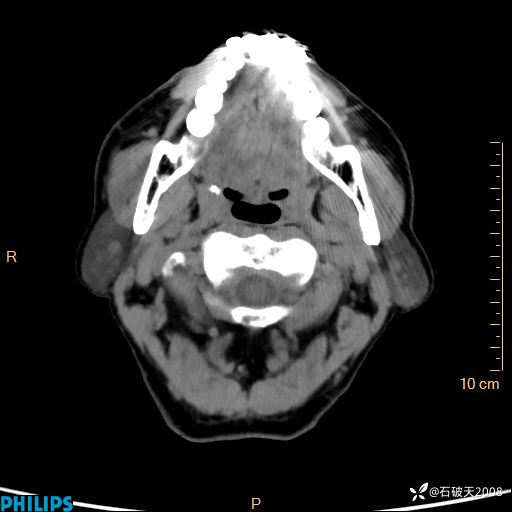

平扫